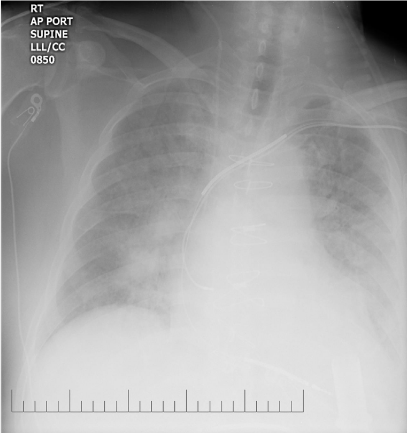

Vital signs on presentation at the outside hospital were: Temperature 38.1 F, Heart Rate of 90-101 beats/minute, Respiratory Rate 20-40 breaths/ minute, mean arterial pressure of 70 mmHg and oxygen saturation of 94% on VentiMask 40%. On examination at our hospital he was found to be tachypneic at 33 breaths/minute requiring Bi-level positive airway pressure (BiPAP), heart rate-106 beats/minute, mean arterial pressure-64 mmHg and oxygen saturation of 90% on VentiMask 40%. He appeared confused and lethargic. Neck exam was positive for jugular venous distension. He had decreased breath sounds bilaterally and the LVAD hum was heard on cardiac exam. On neurologic exam, he did not follow any commands, was aphasic with a right facial droop and had right hemiplegia. On checking with the outside hospital, due to his acute distress and lethargy, a neurologic exam was not performed. Laboratory tests on admission were consistent with hemolysis and acute renal failure (Table 2). LDH was elevated at 3012 (IU/L) up from<500 a week ago. Chest radiography was consistent with pulmonary edema (Figure 1). CT Head revealed a left non-hemorrhagic MCA infarct with mild mass effect and mild midline shift from left to right (Figure 2). Urine in his Foley bag was orange- red in color. A stat echocardiogram (Figure 3) obtained revealed a dilated left and right ventricle and an aortic valve opening every beat that was opening every other beat on his last clinic visit, 3 weeks ago. This further confirmed the working diagnosis of an acute LVAD thrombus complicated by an embolic event leading to the acute ischemic infarct. An emergent Neurology consultation was obtained and after reviewing his physical exam and CT-brain with the Neurology team, the diagnosis of acute ischemic stroke with significant right hemiplegia was confirmed. Since he was outside the recommended treatment window for thrombolytic administration for his acute stroke (9hours against the recommended, the Neurology team recommended against the use of systemic thrombolysis due to the increased risk for bleeding vs. reducing infarct size.

Figure 4 Chest- X Ray Post- Thrombolytic Infusion showing

a) Decreased pulmonary vascular congestion

b) Unchanged LVAD cannula position from baseline